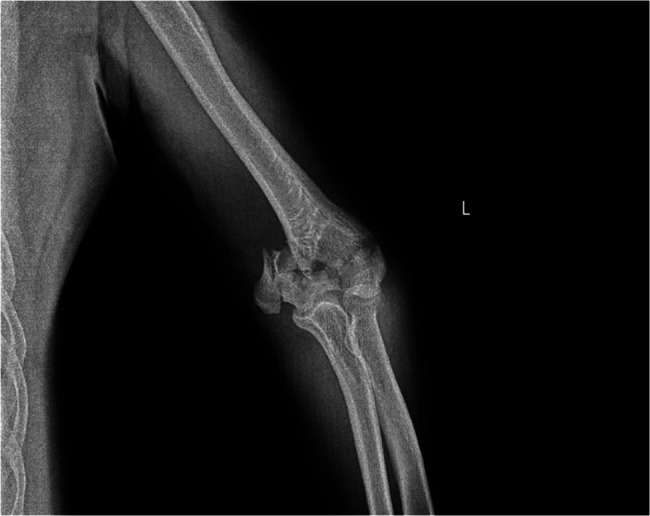

Methods: In this retrospective study, 80 patients over the age of 50 who underwent surgery for AO/OTA type 13-C distal humerus fractures between 2012 and 2022 were analyzed. Patients were categorized into two groups according to the plating technique: parallel(n = 33) or orthogonal(n = 47). Functional and radiological outcomes were compared, including elbow range of motion, Mayo Elbow Performance Score (MEPS), QuickDASH, time to union, complication and reoperation rates, and presence of post-traumatic osteoarthritis. Bone quality was stratified based on HU measurements obtained from preoperative CT scans, specifically from the largest intact slice of the capitellum and trochlea in the sagittal view and from the axial slice just above the proximal fracture line, using a threshold value of 124.5 HU corresponding to the median HU value of the patient cohort. MEPS and QuickDASH were evaluated at the 12-month postoperative follow-up.

Results: Orthogonal plating was associated with longer union times (p < 0.001), higher complication rates (p = 0.008), and greater incidence of post-traumatic arthrosis (p = 0.027) compared to parallel plating. Subgroup analysis revealed that in patients with HU ≤ 124.5, orthogonal plating was linked to significantly increased nonunion risk (p = 0.03) and longer union times (p < 0.001), whereas parallel plating yielded more consistent results regardless of bone quality. Nonunion was significantly higher in the HU ≤ 124.5 subgroup (p = 0.031), and particularly more frequent in orthogonal plating within this group (p = 0.04).